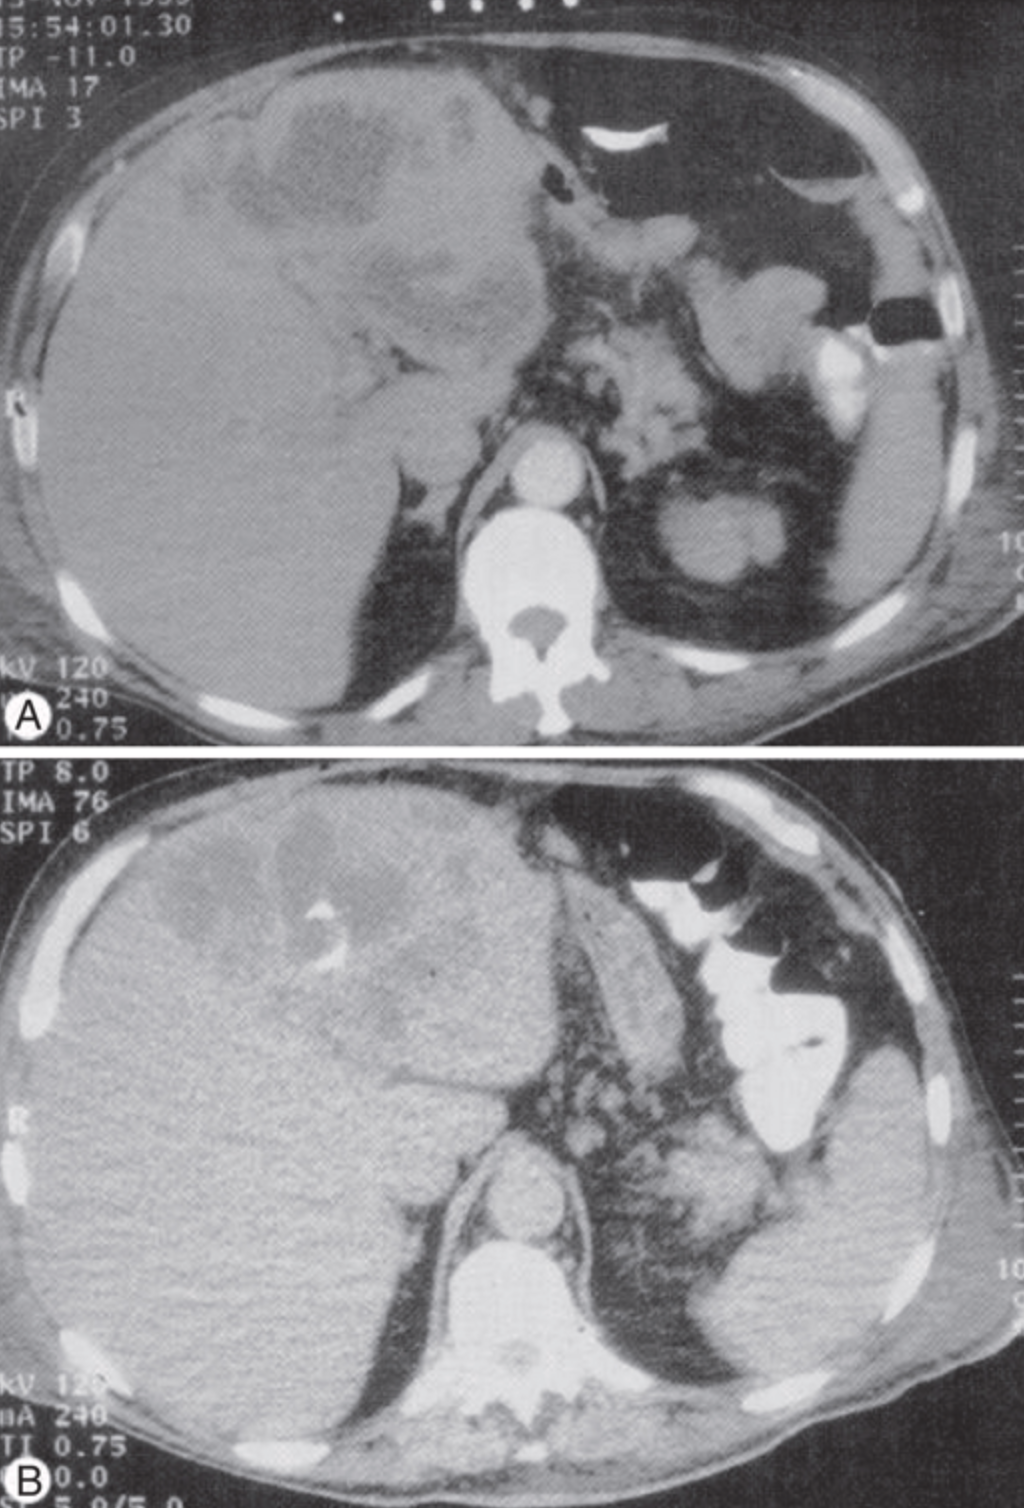

Unlike amebic liver abscess, pyogenic liver abscesses usually require drainage in addition to antibiotic therapy. Percutaneous catheter drainage is the preferred primary therapy, with success rates of 69% to 90%.

Figure 11: CT imaging of pyogenic liver abscess with percutaneous drainage. CT-guided aspiration is the preferred approach for both diagnostic confirmation and therapeutic drainage.